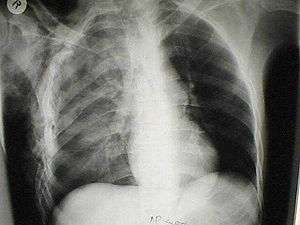

A chest X-ray of a right sided pulmonary contusion associated with flail chest and subcutaneous emphysema | |